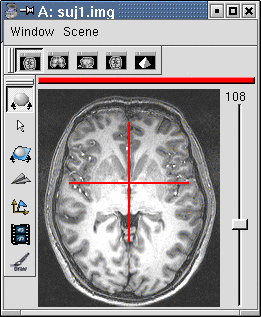

You have to select 3 points (you can use a sagittal slice if you prefer):

- Intersection of anterior commissure with interhemispheric plane;

- Intersection of posterior commissure with interhemispheric plane;

- Any point of the interhemispheric plane not aligned with the previous ones.

Posterior commissure: